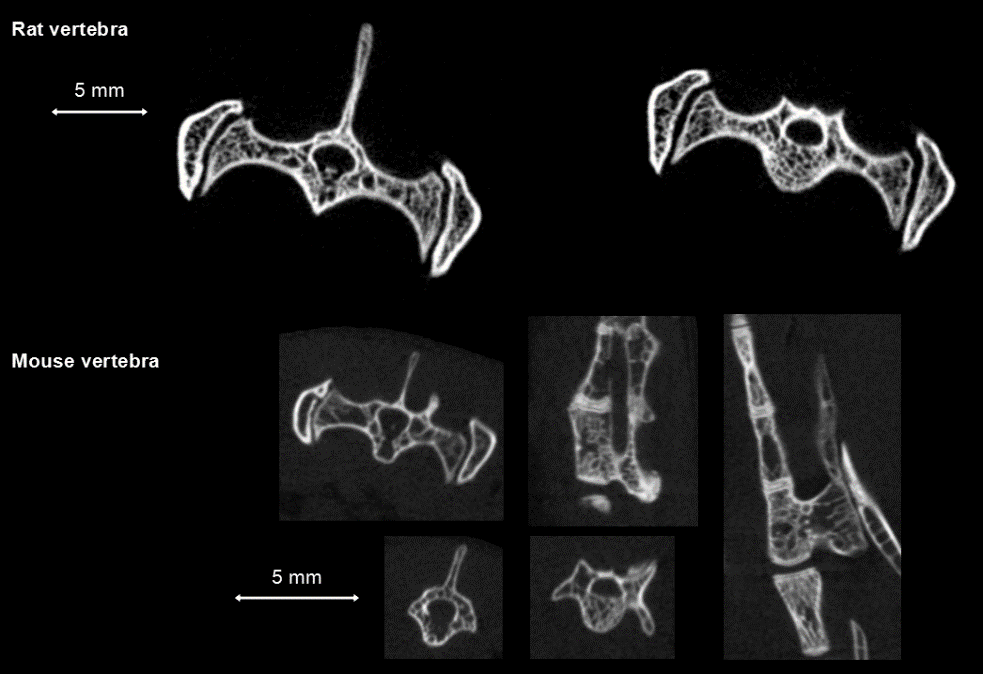

Bone tumor studies: In vivo CT in rats showed that the tumor caused brain and bone metastases, a large number of cavities in the bone, FDK reconstruction, 50µm voxel size.

In vivo measurement of rat tail vertebrae: high resolution ring acquisition, acquisition time: 2min3s, ISRA reconstruction, 50µm voxel size.

In vivo measurement of spinal vertebrae in rats: high definition ring acquisition, acquisition time: 4min, FDK reconstruction, 50 and 20µm voxel size.

Bone data processing with PMOD software: By selecting the region of interest (ROI) on the CT scan image for threshold segmentation and other operations, cortical bone (bone dense) and bone trabeculae (bone cancellous) can be segmulated and extracted into different tissue regions respectively, so as to study and analyze various morphological characteristics of them.